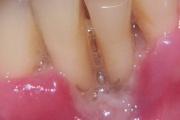

Vali sind huvitav pilt ja me näitame sellega seotud haigust ja sümptomeid